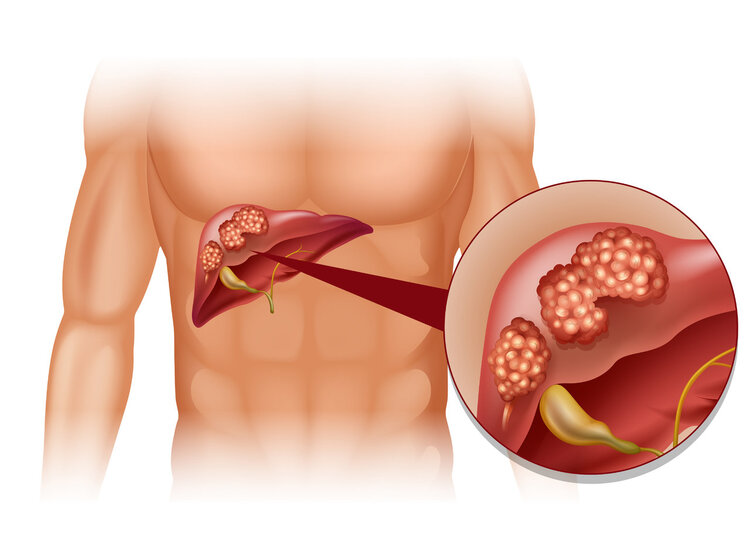

肝癌|早期肝癌不痛不痒,若40岁后身体出现3个症状,建议及时去检查

像小李这样的例子在临床上很常见 , 中年人已经成为肝癌的“主力军” , 一旦发现即是晚期 。 肝癌晚期的治疗难度非常高 , 5年生存率处于所有癌症的下游水平 。

其实 , 肝癌是具有一定高发人群的 , 这些特殊人群一定要引起警惕!

?一、肝癌易盯上这5类人

5、40岁以上人群

肝癌的高发年龄在40岁以上 , 40岁以上的人群建议每年都要做肝癌筛查 。

在临床上 , 大部分肝癌患者确诊时即是晚期 , 早期的发现率非常低 , 这是什么原因导致的 , 一起来往下看 。

二、为什么肝癌一发现就是晚期?

在肝癌早期 , 身体一般不会出现明显症状 , 因为肝脏是个代偿性非常强的器官 , 即便是只剩下30%的肝脏 , 仍然可以正常工作 , 不会出现明显症状 。 当这剩下的30%功能也发生异变时 , 身体才会出现明显症状 , 此时再去检查 , 病情基本上都到了中晚期 。